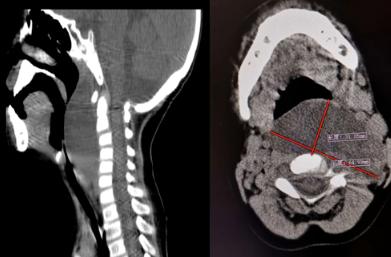

医生查体时发现琪琪左侧颈部肿胀,赶紧为其进行颈部超声和CT查找病因,超声显示:颈部囊实性包块。颈部CT检查发现:患儿咽后壁巨大囊性占位,大小约64mm*31mm*66mm,这一像大鸡蛋样包块将咽喉部填塞,导致呼吸困难。